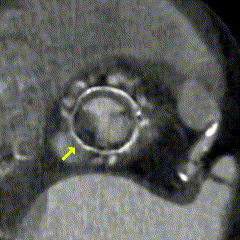

Imagem da Semana

Trombose em prótese valvar aórtica biológica observada à angiotomografia do coração. Observe a restrição de abertura no folheto não-coronariano (seta amarela) em todas as fases do ciclo cardíaco.